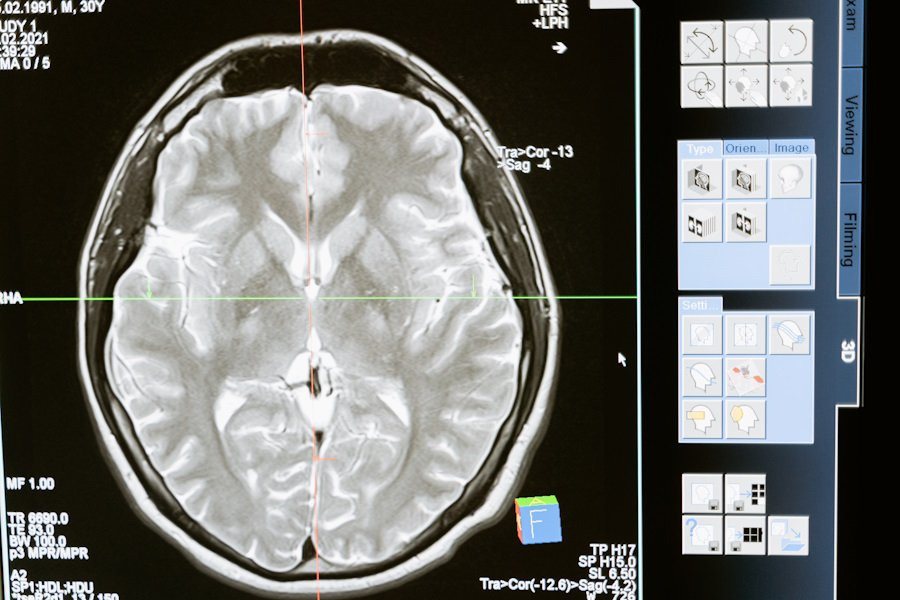

Российские ученые разработали уникальную платформу для борьбы с одной из самых опасных опухолей мозга — глиомой. Этот проект, направленный на улучшение диагностики и лечения, разрабатывается под руководством профессора Галины Павловой в НМИЦ нейрохирургии имени академика Н.Н. Бурденко Минздрава РФ.

Главной особенностью этой платформы является использование аптамеров — молекул, которые способны распознавать опухолевые клетки и не затрагивать здоровые ткани, что значительно уменьшает побочные эффекты. Внедрение этих технологий в клиническую практику может стать революционным шагом в лечении глиомы и других видов рака мозга.